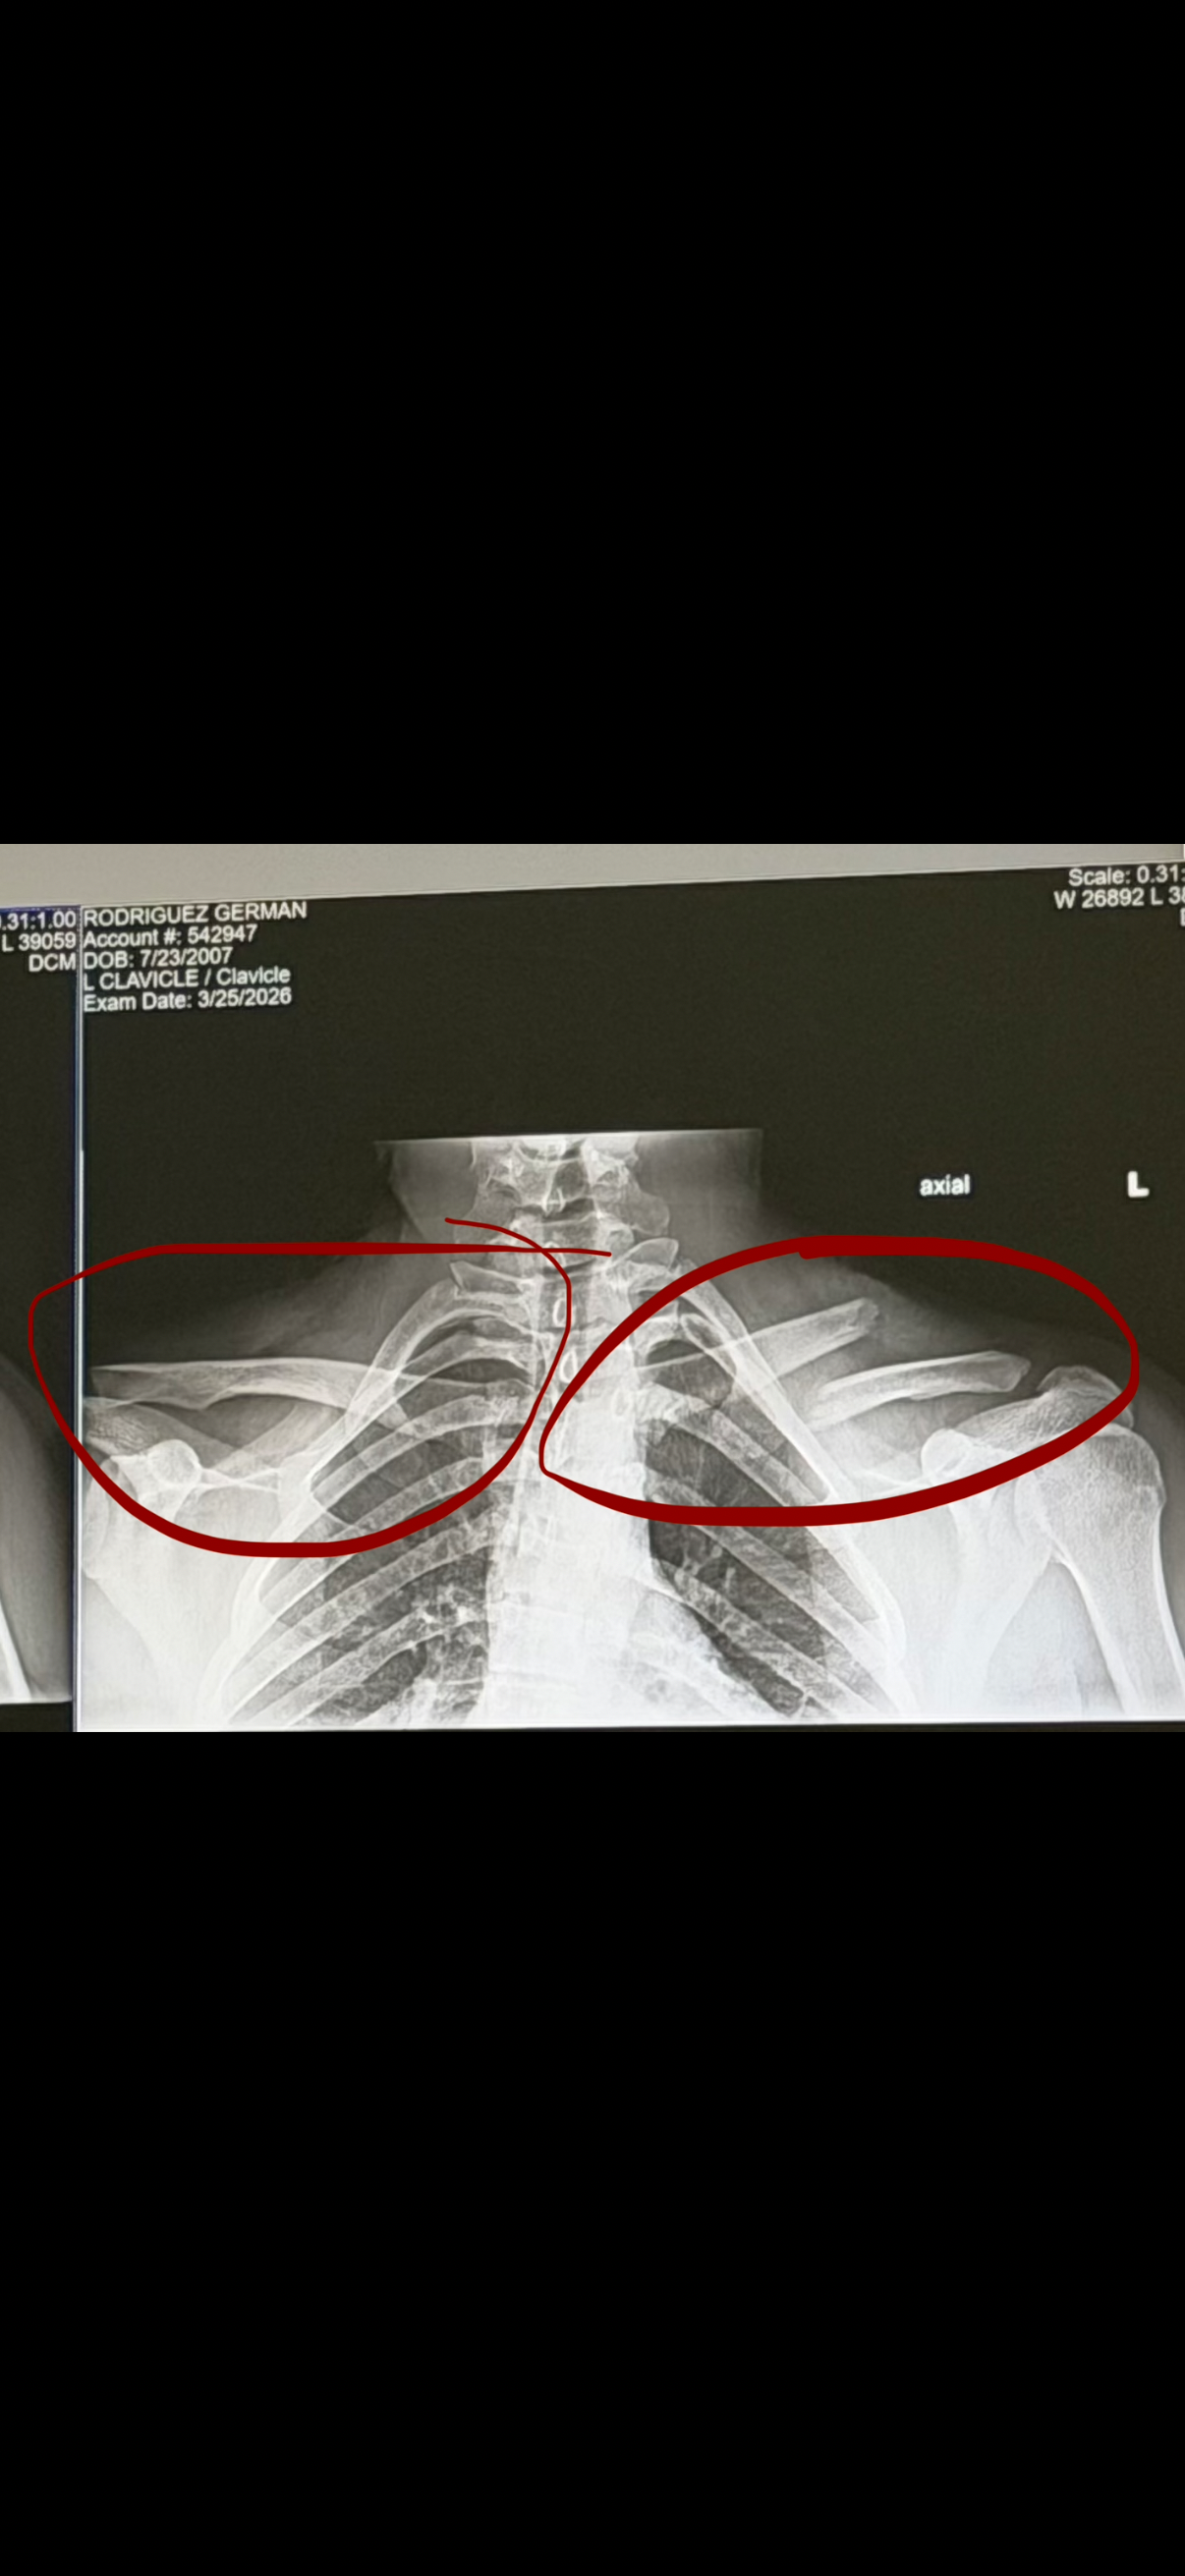

My name is German, and I’m reaching out because I recently had a snowboarding accident that left me with a serious injury to my left clavicle. The doctors have told me I need surgery as soon as possible, but I simply don’t have the funds to cover the medical bills. On top of that, I’ll be unable to work for several months while I recover, which means I’m also worried about how I’ll pay my rent and keep up with basic living expenses.